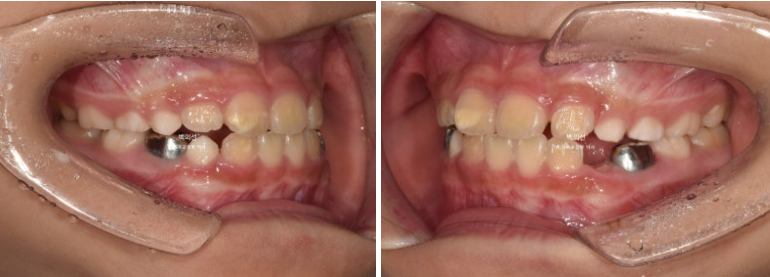

23년 6월, 교정치료를 위해 만7세 어린이가 내원했습니다.

고치고 싶은 것은 비대칭

학교 구강검진에서 중심선이 안맞으니 치료가 필요하다 들어서 오셨습니다.

인비절라인퍼스트의 MA 기능을 이용하여 비대칭을 개선하기로 합니다.

그래서 23년 11월 다시 내원하여 앞니 4개가 모두 나온 것을 확인하고 정밀진단을 했습니다.

23.12

앞니 중심선이 맞지 않고

엑스레이에서 아래턱의 골격적 비대칭으로 진단이 되었습니다.

인비절라인퍼스트 치료를 권유드렸고 아래턱의 위치를 중앙으로 재위치시키는 Mandible Advance(MA) 기능을 통해 비대칭 개선을 목표로 치료계획을 세웠습니다.